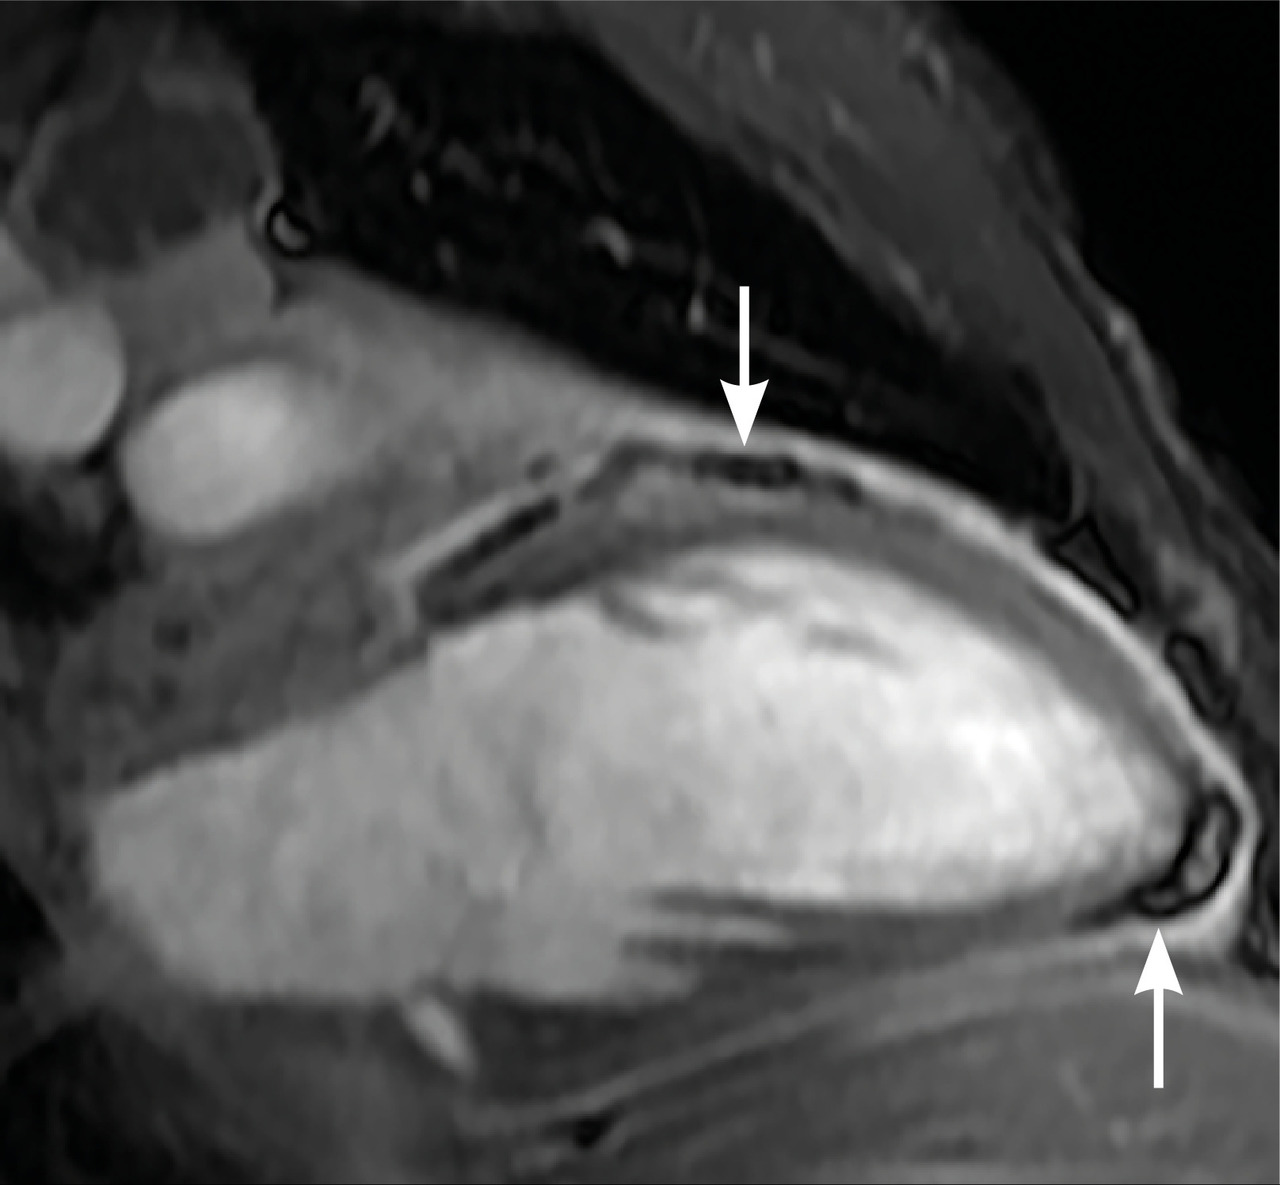

L’imagerie montrait : sur la tomodensitométrie (TDM) thoracique une miliaire tuberculeuse pulmonaire et des adénopathies médiastinales ; sur l’imagerie par résonance magnétique (IRM) du rachis une spondylodiscite T11-T12 (fig. 1 ) ; sur la TDM abdominale des abcès paravertébraux de T9 à T12 le long des psoas (fig. 2 , flèches blanches) et des lésions micronodulaires hépatiques multiples (fig. 2 , flèche jaune) ; sur l’IRM myocardique des signes de péricardite (fig. 3 , flèches). La ponction lombaire montrait une méningite. Un tuberculome était visible sur l’IRM cérébrale, entouré d’un œdème périlésionnel (fig. 4 ). Le diagnostic de tuberculose disséminée était prouvé par polymerase chain reaction sur une ponction d’abcès. Compte tenu de l’atteinte neuroméningée, un traitement adjuvant par corticothérapie s’imposait dans le cas présent, de même qu’une antibiothérapie de 9 à 12 mois.1

L’imagerie montrait : sur la tomodensitométrie (TDM) thoracique une miliaire tuberculeuse pulmonaire et des adénopathies médiastinales ; sur l’imagerie par résonance magnétique (IRM) du rachis une spondylodiscite T11-T12 (